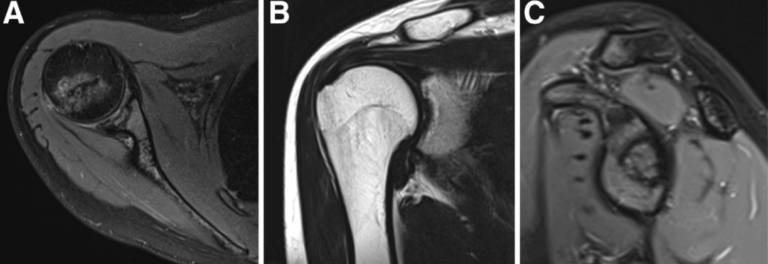

Alessandro Donà M.D. | Rocco Bonfatti M.D. | Chiara Manzini M.D. | Elisa De Santis Ph.D. | Gian Mario Micheloni M.D. | Andrea Giorgini M.D.